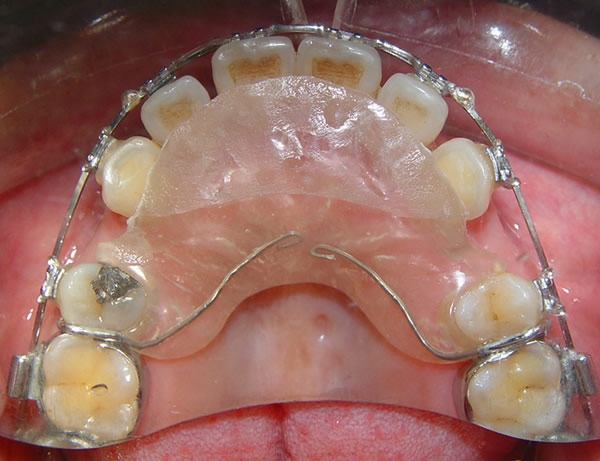

二、正畸治疗

1、活动矫治器? 矫治器是一种治疗错合畸形的装置,或称正畸矫治器。它可产生作用力,或由咀嚼肌口周肌功能作用力藉矫治器使畸形的颌骨、错位牙齿及牙周支持组织发生变化,以利于牙颌面正常生长发育。活动矫治器是一种由患者自行摘戴的矫治装置,因而又称可摘矫治器。它是由基托、固位体、各种弹簧所组成。使用活动矫治器必须严格选择适应证,认真加力,患者合作才能保证疗效。

常见的活动矫治器有:

(1)平导---用于打开咬合(压低下前牙)

(2)唇挡---限制上前牙前突、

(3)扩弓---扩大牙弓

(4)功能性矫治器---促进或限制颌骨的生长发育

(5)舌习惯矫治器

(6)固定正畸治疗结束后都要做的活动保持器也是其中的一种。

活动矫治器在使用过程中,患者是否合作很关键,大多数应用活动矫治器的是少年儿童,他们的自觉性不是很好,这种矫治器本身由于基托大、卡环多、加力弹簧力量不均匀,有的还得戴在嘴里吃饭、睡觉是不太舒服,有时还需自己加橡皮牵引圈。没有好的自觉性是不能保证疗效的。不配合的儿童往往与家长的教育方式也有一定的关系,当然做家长的也应体谅小孩的不适反应。